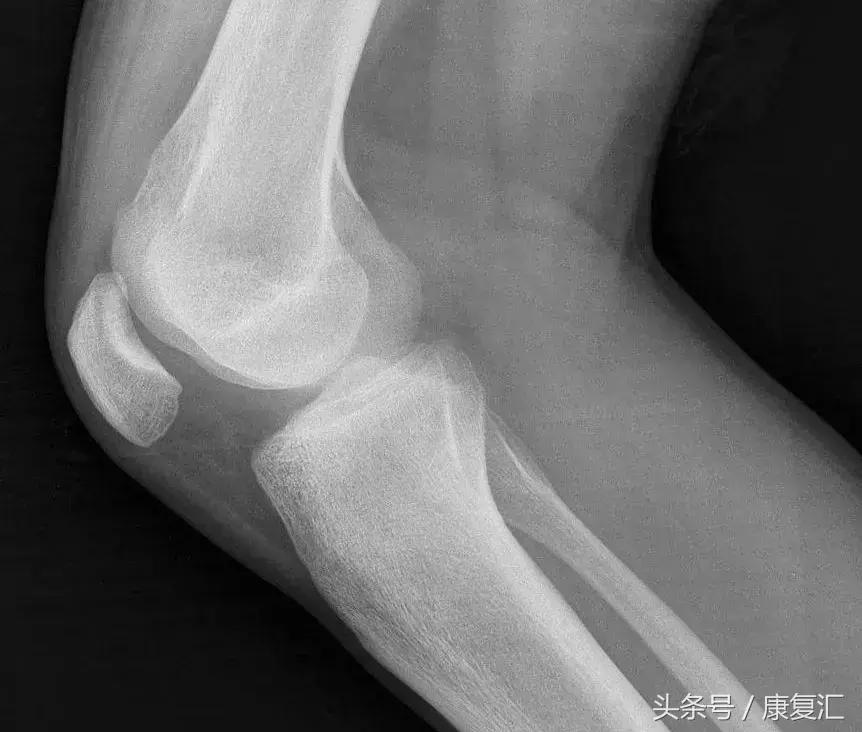

X 线片可见关节周围软组织肿胀,骨退行性改变和骨质局限性疏松。积液明显时,关节间隙增宽。

此外,值得注意的是应与结核性滑膜炎鉴别。后者也为一种慢性滑膜炎,发展到一定时期将表现出结核中毒症状。X 线片上早期骨质疏松较严重,到后期破坏软骨而出现关节面不规则破坏及间隙狭窄。